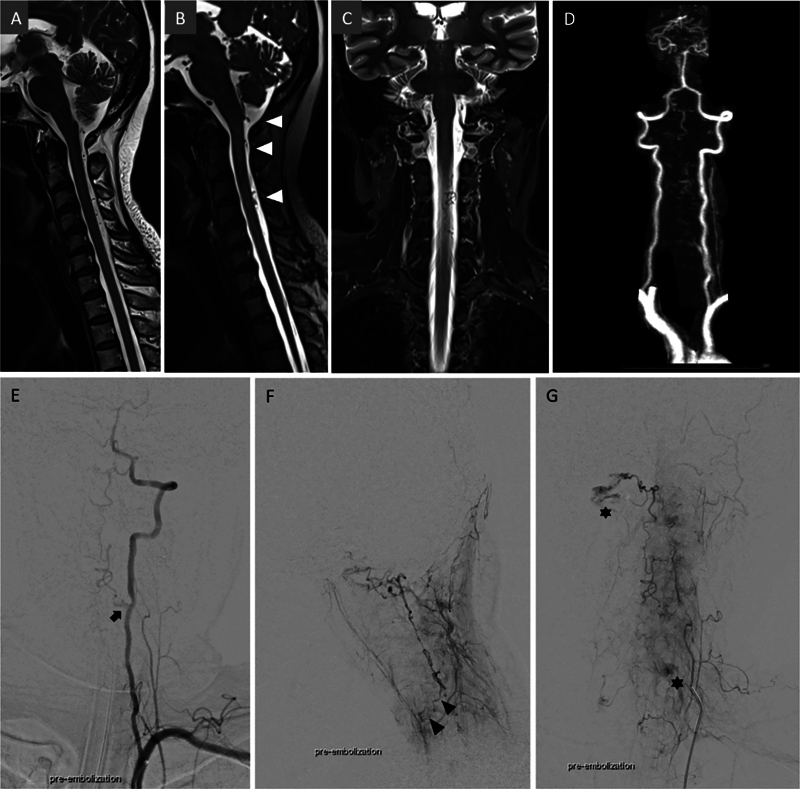

下颈动静脉瘘(AVFs)是一种罕见而复杂的血管畸形,由于其位置和表现多变,给临床带来了重大挑战。虽然上颈椎avf已被广泛研究,但下颈椎avf仍未得到充分研究。本研究旨在回顾下颈椎avf患者的临床表现、治疗策略和结果,以提高对治疗方法的认识和改进。我们对2006年6月至2023年12月期间在我院治疗的脊柱血管畸形患者进行了回顾性分析,确定了2例下颈椎avf。此外,采用Ovid MEDLINE、PubMed和Cochrane等数据库,按照系统评价和荟萃分析指南的首选报告项目,对44例下颈椎avf患者进行了系统文献综述。收集的数据包括患者人口统计学、临床表现、瘘管类型、动脉和静脉受累、治疗方式和神经预后。包括我们2例在内的44例下颈椎avf患者中,50%为女性,平均年龄48.68岁(范围4-76岁)。临床表现各不相同,27.3%出现出血,18.2%出现脊髓病,18.2%无症状。静脉引流方式在症状严重程度中起着重要作用,复杂的髓周静脉引流和逆行静脉引流会导致更差的结果。治疗方式包括血管内栓塞(40.9%)、手术切除(25%)和联合入路(18.2%),54.5%的病例恢复良好。下颈椎avf由于其不同的表现和复杂的血管解剖结构而面临多种临床挑战。早期诊断和量身定制的管理,包括血管内栓塞和手术切除,是优化患者预后的必要条件。需要进一步研究以更好地了解无症状房颤的自然史并改进治疗方案。

Lower cervical arteriovenous fistulas (AVFs) are rare and complex vascular malformations that pose significant clinical challenges due to their location and variable presentation. While upper cervical AVFs have been extensively studied, lower cervical AVFs remain underresearched. This study aims to review the clinical presentations, management strategies, and outcomes of patients with lower cervical AVFs to enhance understanding and improve treatment approaches. We conducted a retrospective analysis of patients with spinal vascular malformations treated at our institute between June 2006 and December 2023, identifying two cases of lower cervical AVFs. Additionally, a systematic literature review was performed following the Preferred Reporting Items for Systematic Reviews and Meta-Analyses guidelines, including 44 patients with lower cervical AVFs, using databases such as Ovid MEDLINE, PubMed, and Cochrane. Data collected included patient demographics, clinical presentation, fistula type, arterial and venous involvement, treatment modality, and neurological outcomes. Among the 44 patients with lower cervical AVFs, including our two cases, 50% were female, and the mean age was 48.68 years (range: 4-76 years). Clinical presentations varied, with 27.3% experiencing hemorrhage, 18.2% presenting with myelopathy, and 18.2% remaining asymptomatic. Venous drainage patterns played a significant role in symptom severity, with complex perimedullary and retrograde venous drainage contributing to worse outcomes. Treatment included endovascular embolization (40.9%), surgical resection (25%), and combined approaches (18.2%), with good recovery achieved in 54.5% of cases. Lower cervical AVFs present diverse clinical challenges due to their variable presentations and complex vascular anatomy. Early diagnosis and tailored management, including endovascular embolization and surgical resection, are essential for optimizing patient outcomes. Further research is needed to better understand the natural history of asymptomatic AVFs and improve treatment protocols.